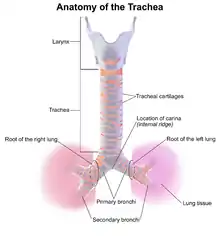

An adult's trachea has an inner diameter of about 1.5 to 2 centimetres (1⁄2 to 3⁄4 in) and a length of about 10 to 11 cm (4 to 4+1⁄4 in), wider in males than females.[2] The trachea begins at the lower edge of the cricoid cartilage of the larynx[3] at the level of sixth cervical vertebra (C6)[2] and ends at the carina, the point where the trachea branches into left and right main bronchi.[2], at the level of the fourth thoracic vertebra (T4),[2] although its position may change with breathing.[3] The trachea is surrounded by 16–20 rings of hyaline cartilage; these 'rings' are 4 millimetres high in the adult, incomplete and C-shaped.[2] Ligaments connect the rings.[3] The trachealis muscle connects the ends of the incomplete rings and runs along the back wall of the trachea.[3] Also adventitia, which is the outermost layer of connective tissue that surrounds the hyaline cartilage, contributes to the trachea's ability to bend and stretch with movement.[4]

Although trachea is a midline structure, it can be displaced normally to the right by the aortic arch.[5]

In front of the upper trachea lies connective tissue and skin.[2] Several other structures pass over or sit on the trachea; the jugular arch, which joins the two anterior jugular veins, sits in front of the upper part of the trachea. The sternohyoid and sternothyroid muscles stretch along its length. The thyroid gland also stretches across the upper trachea, with the isthmus overlying the second to fourth rings, and the lobes stretching to the level of the fifth or sixth cartilage.[2] The blood vessels of the thyroid rest on the trachea next to the isthmus; superior thyroid arteries join just above it, and the inferior thyroid veins below it.[2] In front of the lower trachea lies the manubrium of the sternum, the remnants of the thymus in adults. To the front left lie the large blood vessels the aortic arch and its branches the left common carotid artery and the brachiocephalic trunk; and the left brachiocephalic vein. The deep cardiac plexus and lymph nodes are also positioned in front of the lower trachea.[2]

Behind the trachea, along its length, sits the oesophagus, followed by connective tissue and the vertebral column.[2] To its sides run the carotid arteries and inferior thyroid arteries; and to its sides on its back surface run the recurrent laryngeal nerves in the upper trachea, and the vagus nerves in the lower trachea.[2]

Blood and lymphatic supply

The upper part of trachea receives and drains blood through the inferior thyroid arteries and veins;[2] the lower trachea receives blood from bronchial arteries.[3] Arteries that supply the trachea do so via small branches that supply the trachea from the sides. As the branches approach the wall of the trachea, they split into inferior and superior branches, which join with the branches of the arteries above and below; these then split into branches that supply the anterior and posterior parts of the trachea.[3] The inferior thyroid arteries arise just below the isthmus of the thyroid, which sits atop the trachea. These arteries join (anastamoses) with ascending branches of the bronchial arteries, which are direct branches from the aorta, to supply blood to the trachea.[2] The lymphatic vessels of the trachea drain into the pretracheal nodes that lie in front of the trachea, and paratracheal lymph nodes that lie beside it.[2]